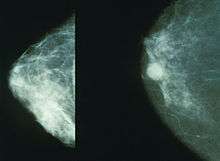

Normal (left) versus cancerous (right) mammography image.